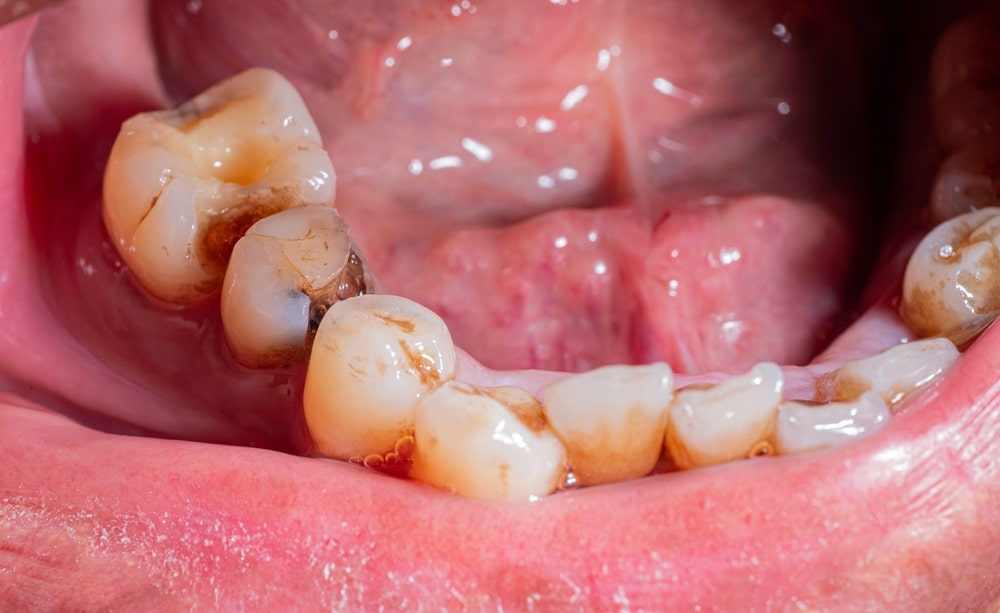

Dental Cavities (Tooth Decay)

When bacteria in your mouth produce acids that erode tooth enamel, cavities form.

Initially, they might cause no pain, but as they deepen and reach the inner layers of the tooth, they can lead to sharp pain, especially when consuming hot, cold, or sweet foods and drinks.

This is the primary cause of toothaches for many individuals. Teeth whitening service will assist your teeth regain color.